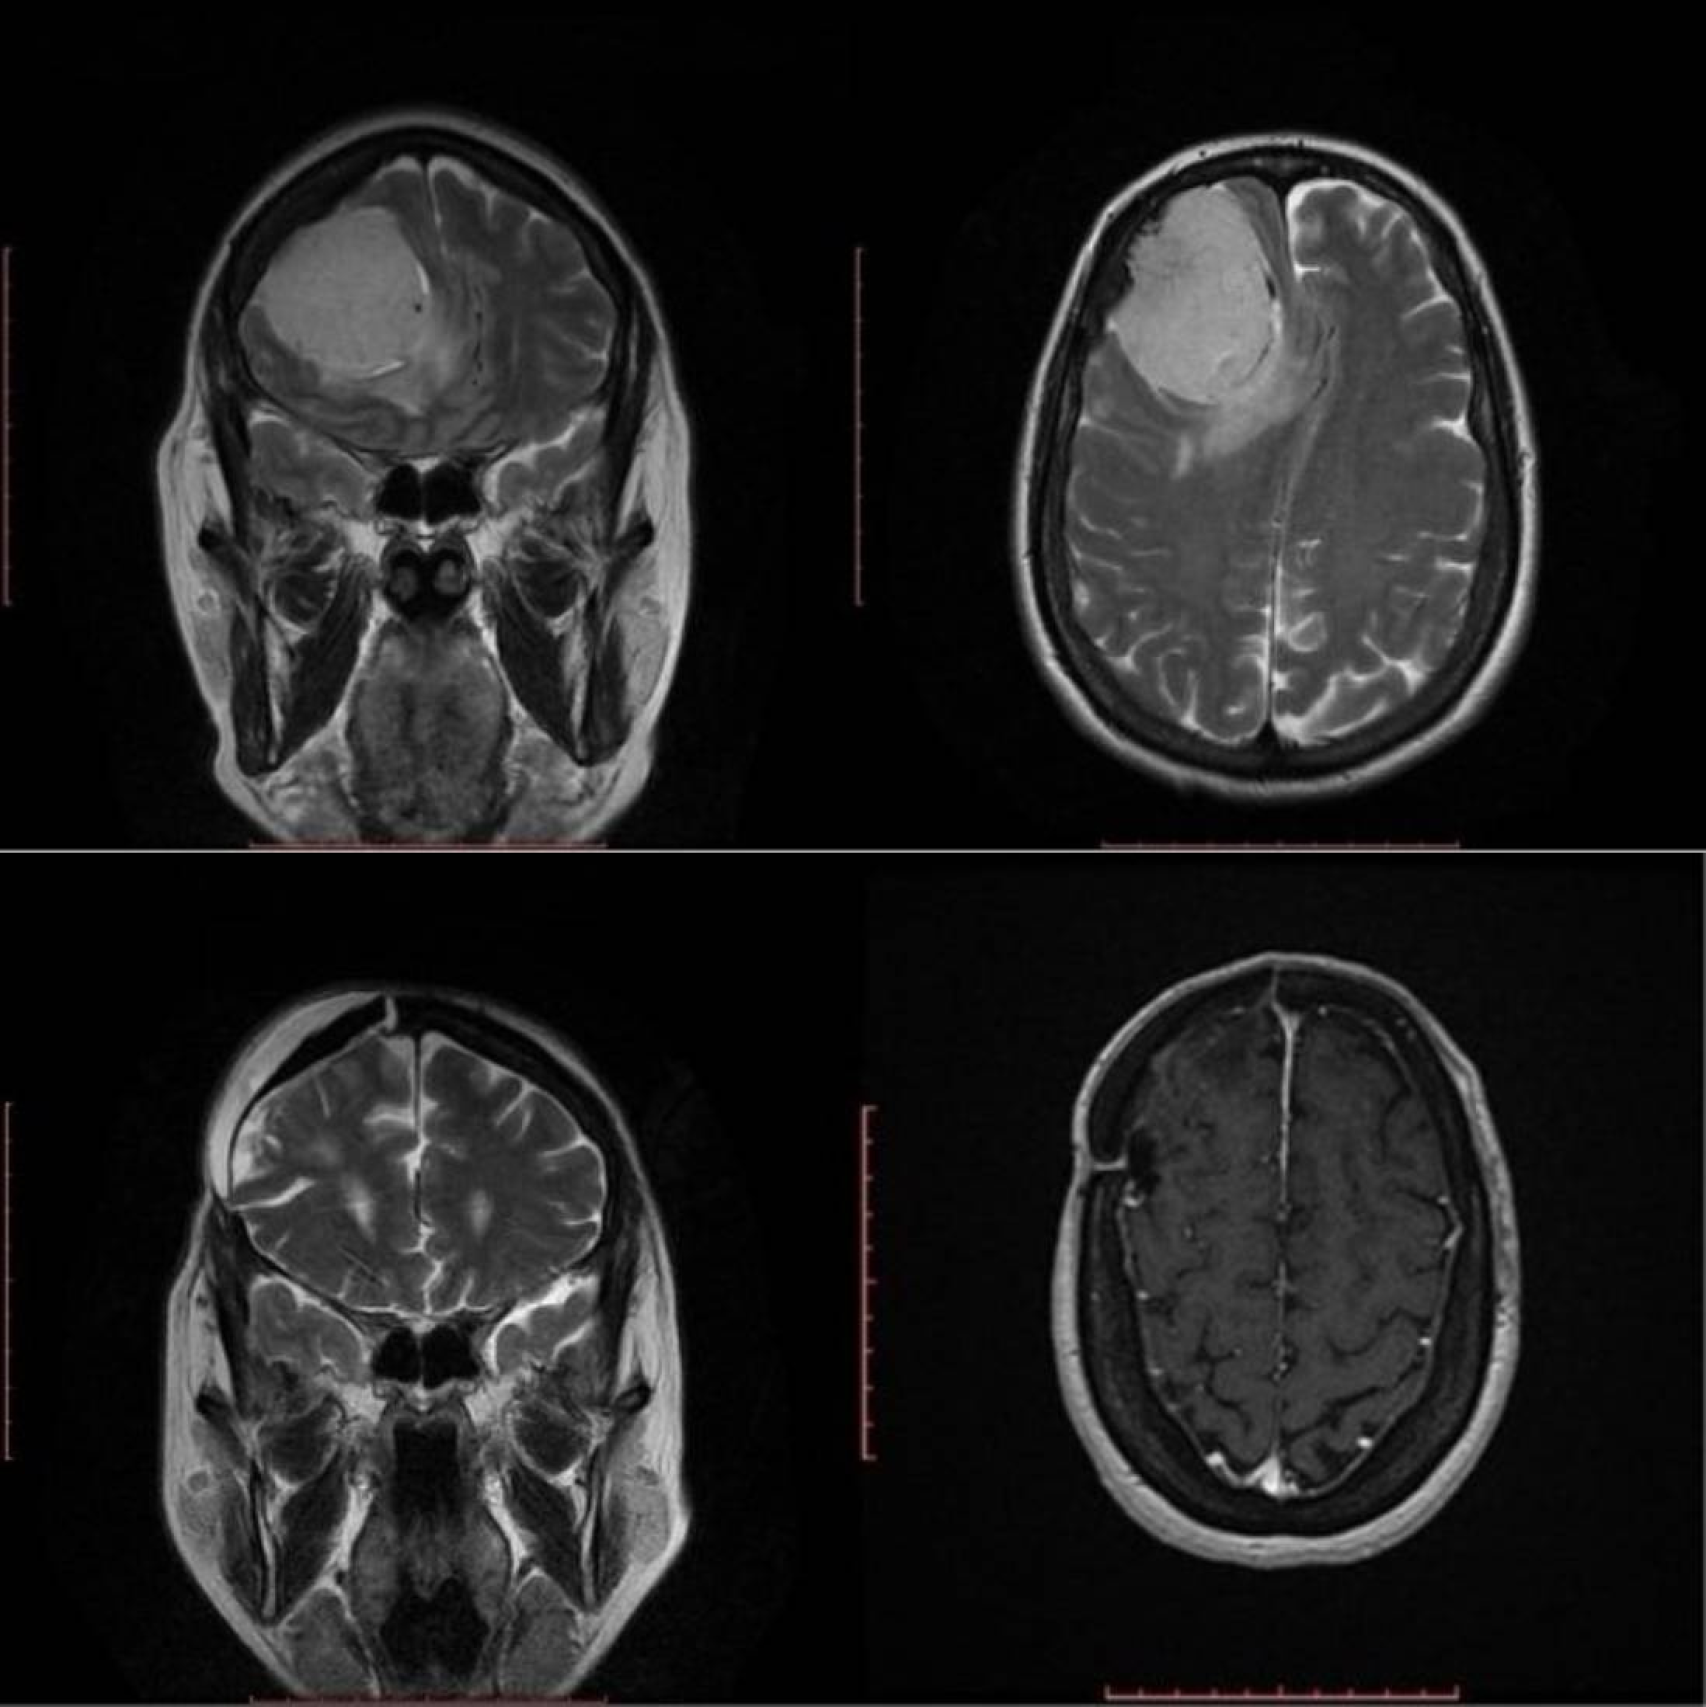

Imagen de una lesión tumoral antes y después de la cirugía.

Imagen de una lesión tumoral antes y después de la cirugía. Quirónsalud